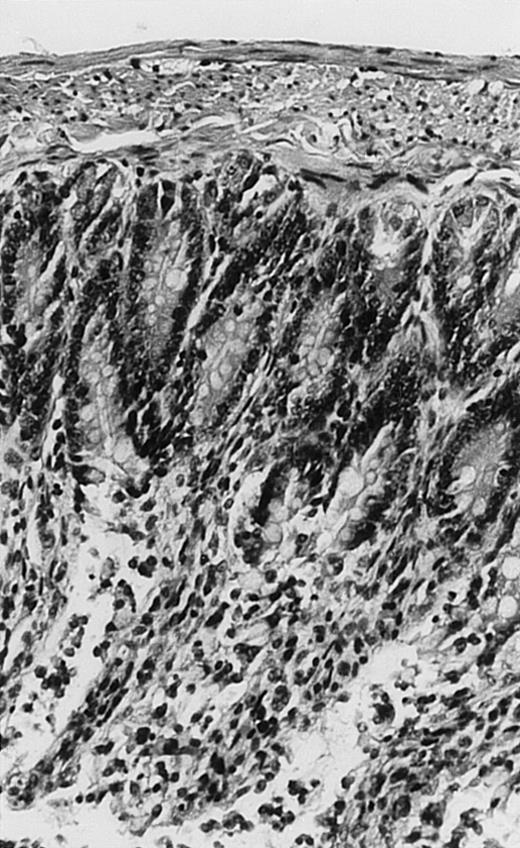

Pathologic findings in the small and large intestine were strikingly different depending on the treatment group. Figure 2A shows a representative pathologic sample from an animal assigned to the control group. Marked thinning of the bowel wall and extensive areas of epithelial cell sloughing was noted. Animals randomized to rhG-CSF treatment had minimal improvement in histologic findings with focal regions of preserved epithelium (Fig2B). Animals randomized to the rhIL-11 group showed substantial improvement with thickening of the epithelial layer and preservation of mucosal cell integrity (Fig 2C). Animals receiving both rhG-CSF and rhIL-11 had the most favorable histologic findings with normal mucosal thickness, minimal inflammatory changes, and preserved tissue architecture (Fig 2D). The composite analysis of the gastrointestinal pathology is provided in Table 1.

Histopathology of small intestinal mucosa cut in transection from an animal in each treatment group (study day 8). The upper panel (row 1) is a low power view (original magnification × 57); the lower panel (row 2) is a high power view (original magnification × 144). Note the diffuse thinning and necrosis of the mucosa with sloughing of intestinal epithelial cells in the control animal (A). There is progressive recovery of the thickness of the mucosa, reduction in inflammatory changes, and improved epithelial architecture with rhG-CSF (B), rhIL-11 (C), and combination therapy with rhG-CSF+IL-11 (D).